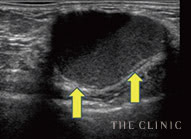

オイルシスト

しこり内部の壊死した脂肪がオイル状になっているしこりは、エコーで黒く映し出されます。

石灰化

被膜にカルシウムの結晶が沈着したしこりはエコーで投影できず、深部が黒く映ります。

瘢 痕

しこりから壊死脂肪が漏れて炎症すると、しこりが瘢痕化。エコー鑑別が難しい症例です。

実際のエコー画像

治療前